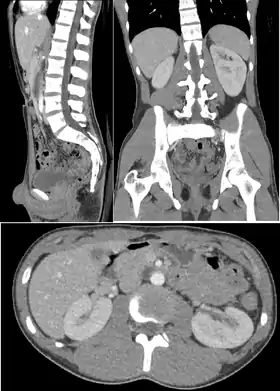

Abdomen and pelvis

CT is an accurate technique for diagnosis of abdominal diseases like Crohn's disease,[64] GIT bleeding, and diagnosis and staging of cancer, as well as follow-up after cancer treatment to assess response.[65] It is commonly used to investigate acute abdominal pain.[66]

Non-enhanced computed tomography is today the gold standard for diagnosing urinary stones.[67] The size, volume and density of stones can be estimated to help clinicians guide further treatment; size is especially important in predicting spontaneous passage of a stone.[68]

Multiplanar reconstruction and projections

Multiplanar reconstruction (MPR) is the process of converting data from one anatomical plane (usually transverse) to other planes. It can be used for thin slices as well as projections. Multiplanar reconstruction is possible as present CT scanners provide almost isotropic resolution.[106]

MPR is used almost in every scan. The spine is frequently examined with it.[107] An image of the spine in axial plane can only show one vertebral bone at a time and cannot show its relation with other vertebral bones. By reformatting the data in other planes, visualization of the relative position can be achieved in sagittal and coronal plane.[108]